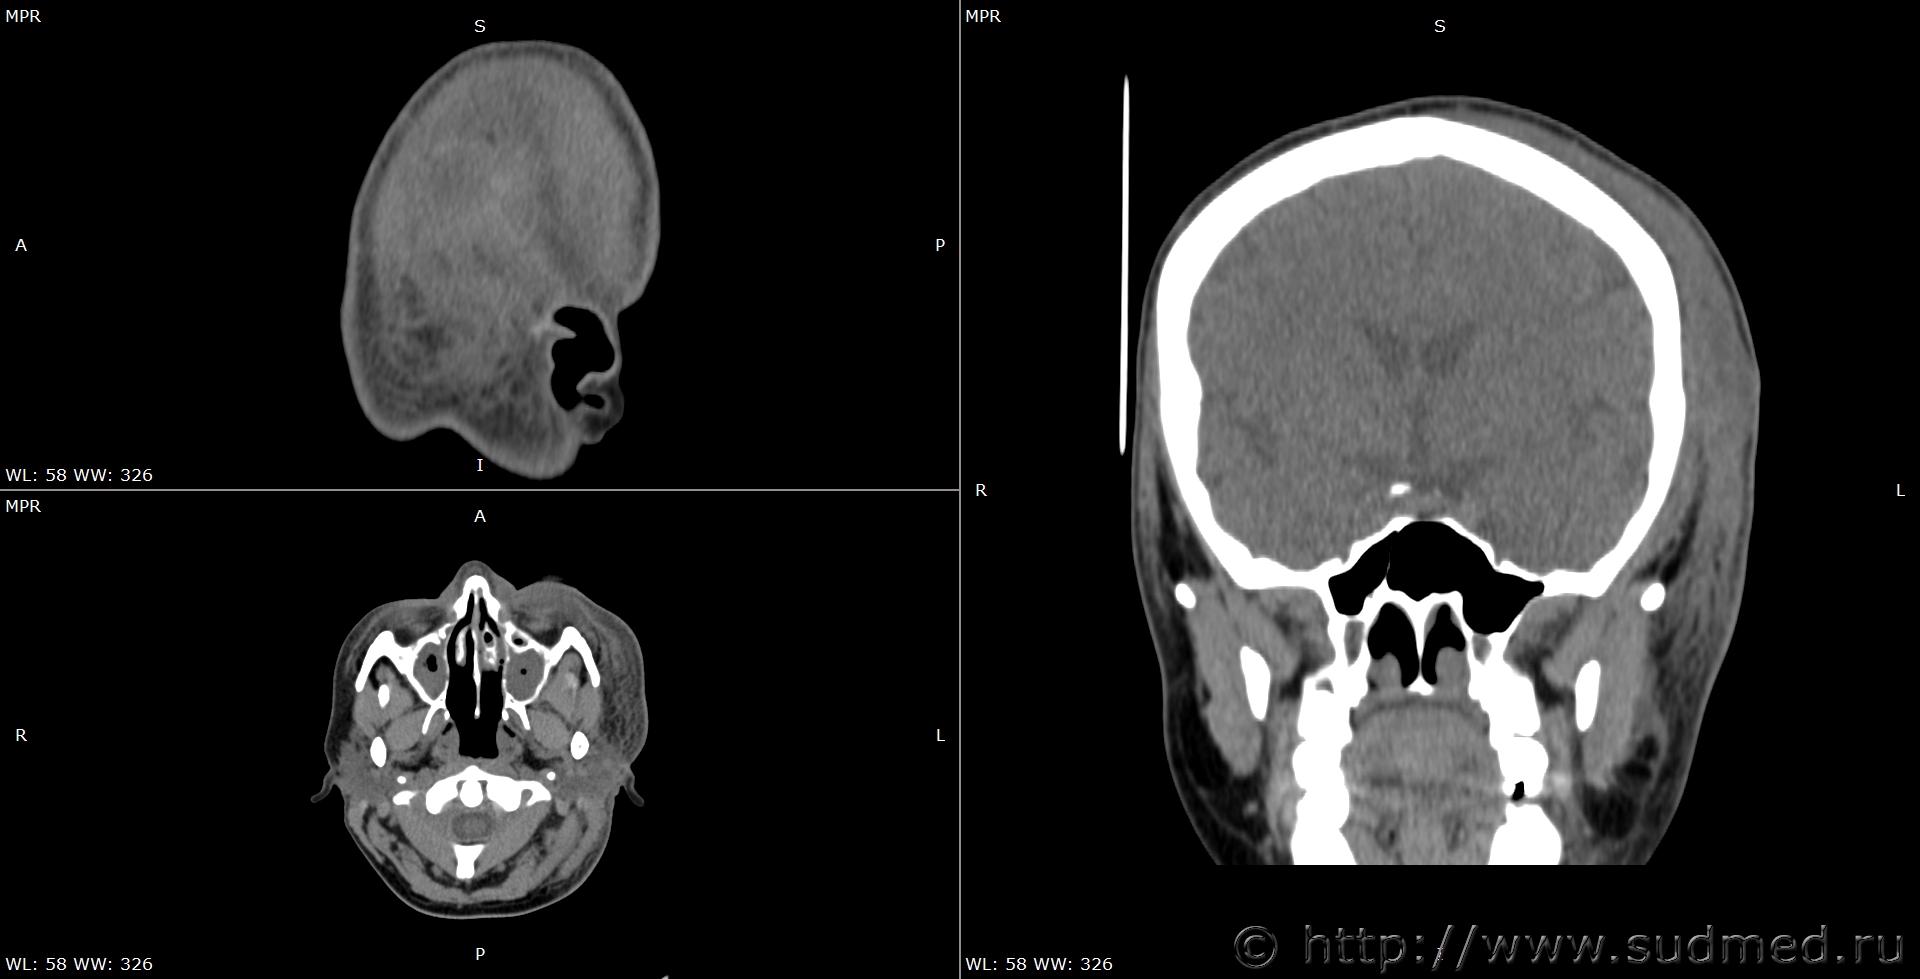

При экспертизе живого лица по медицинским документам встретились переломы шиловидных отростков височных костей. Женщина 39 лет, обратилась за медицинской помощью на 5-е сутки после травмы, тогда же провели РКТ. До этого никуда не обращалась. В протоколе РКТ отметили перелом шиловидного отростка левой височной кости, на снимках перелом на границе верхней и средней трети, дистальный отломок слегка смещен кпереди, каких-либо признаков заживления нет. Длина отростка 2,19 см. Судебная медицина - Прикрепленное изображение Также на КТ визуализируется перелом шиловидного отростка правой височной кости в нижней трети с выраженным смещением, думаю, отрывного характера (его длина 2,01 см), также без каких-либо признаков заживления Судебная медицина - Прикрепленное изображение; и гематома теменной области слева с переходом, в частности, на левую височную область, область левого сосцевидного отростка, левые околоушно-жевательную и скуловую области, левую боковую поверхность шеи Судебная медицина - Прикрепленное изображение, увеличение в объеме, нечеткость контура и разволокнение левой грудино-ключично-сосцевидной мышцы и левой ременной мышцы головы в верхней трети Судебная медицина - Прикрепленное изображение, вокруг них, в том числе кнутри от ременной мышцы, повышение плотности ПЖК Судебная медицина - Прикрепленное изображение; такие же изменения плюс повышение плотности левой подкожной мышцы шеи Судебная медицина - Прикрепленное изображение, увеличение в объеме и нечеткость контура левой околоушной слюнной железы, левая жевательная мышца не изменена Судебная медицина - Прикрепленное изображение. У подъязычной кости вижу нарушения целостности левого большого рога, но окостенение не завершено, края четко не визуализируются, поэтому о характере нарушений целостности не могу судить. Судебная медицина - Прикрепленное изображение Судебная медицина - Прикрепленное изображение В осмотрах врачей какие-либо изменения в области шеи, изменения голоса, соответствующие жалобы не отмечены; на 6-е сутки выставили острый фарингит. Помимо этой травмы есть переломы костей носа, там ничего особенного.

Расцениваю как лёгкий по длительности, перелом всё-таки никак не затрагивает внутреннюю костную пластинку черепа, и отломок жизненно важные структуры не задел.